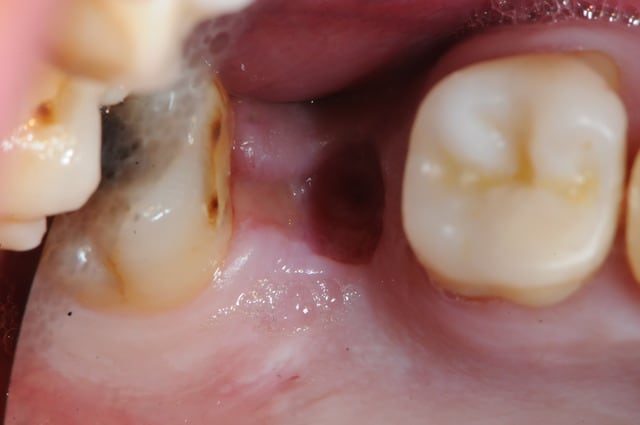

1&2: prélèvement sanguin pour centrifugation et réalisation de membranes de PRF

3: vue occlusale: plus ou pas d'écoulement purulent

le patient a été placé sous orelox depuis samedi avec pulvérisation nasale 3x/j d'actisoufre

1&2 : réalisation à l'aide d'une tréphine de la fenêtre vestibulaire pour aller plus vite et surtout pour pouvoir réutiliser plus tard ce petit bloc osseux.

3: fenêtre et CBS bien visibles

vous noterez tout de suite la différence de teinte entre un sinus sain et avec ici, un sinus hyper inflammatoire et infecté (une vraie cocotte-minute)